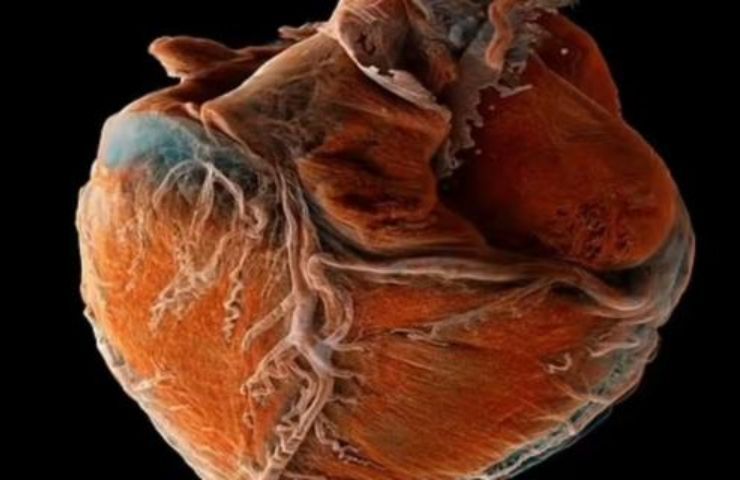

Un importante studio condotto dall’European Synchrotron Radiation Facility di Grenoble in collaborazione con l’University College di Londra ha permesso di mettere a confronto un cuore umano malato con uno sano, grazie a un atlante 3D. Tutto quello che c’è da sapere.

Di recente è stato possibile ottenere il primo atlante 3D di un cuore sano messo in relazione e in confronto con uno non sano. Tutto ciò è stato reso possibile da un lavoro senza precedenti condotto dall’European Synchrotron Radiation Facility di Grenoble in simbiosi con l’University College di Londra.

La mappatura del cuore umano è stata definita in modo abbastanza indicativo dai ricercatori che hanno dato vita al tutto. Sono state usate, infatti, queste parole: “L’equivalente di Google Earth per il cuore umano“.

Gli esperti si sono serviti di una tecnica a raggi X per ottenere preziose informazioni da un cuore sano e da un cuore malato di due persone decedute. Questo vero e proprio atlante 3D riguarda sia l’intero organo del nostro corpo che le singole cellule, i vasi sanguigni e le valvole.

Questo studio ha davvero una importanza capitale, dal momento che consentirà di valutare e capire meglio tutti i disturbi del cuore. Grazie a questo atlante 3D, quindi, i medici potranno ottenere informazioni nuove e valutare in modo più efficace le cure da effettuare.

La tecnica a raggi X usata dai ricercatori consente di mostrare le singole cellule dell’organo. Si sono ottenute delle perfette immagini in 3D complete e dettagliate nei minimi particolari. Esse sono incentrate sull’assorbimento e sulla rifrazione dei raggi X da parte dei tessuti.

Queste sono state le sue parole in merito: “L’atlante che abbiamo creato ci permette di visualizzare l’intero organo su scala globale e poi di zoomare per osservare le caratteristiche cardiovascolari con un dettaglio senza precedenti“.

Il professore ha anche detto ciò: “Essere in grado di mappare interi organi in questo modo rivela dettagli e collegamenti finora sconosciuti“. La tecnica sarà usata anche per confrontare diversi altri organi del corpo umano, in modo tale da fornire informazioni davvero molto preziose per la nostra salute.